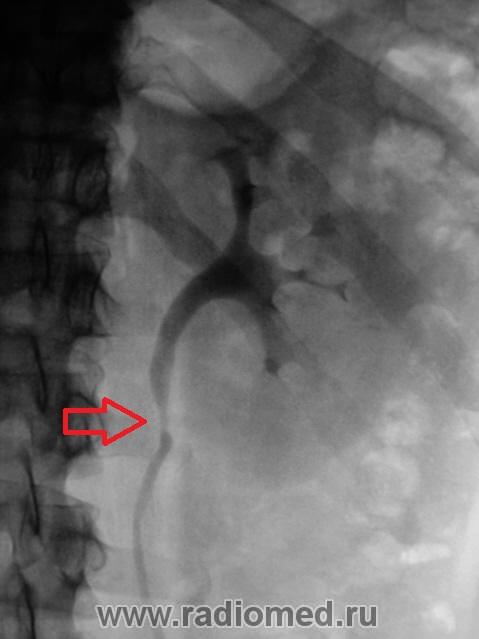

Почки контурируются в типичном месте, обычной формы и размеры. R-позитивных уроконкрементов в проекции мочевыносящих путей на обзорной урограмме не выявлено. ЧЛС контрастированы синхронно, не расширены. Мочеточники контрастированы, левый просматривается на всем протяжении, в нижней 1/3 незначительно стойко расширен, оттеснен кверху и вправо (хотя возможен такой вариант расположения устьев мочеточников - к сожалению правый мочеточник не визуализируется т.е. несчем сравнить). В мочевом пузыре, слева от срединной линии, дефект наполнения с четкой неровной границей.

Мы решили сразу после исследования сделать томографию мочевого пузыря.

Меня немного смутило сужение мочеточника у левой почки, возможно перистальтика. Прошу обратить внимание.

Что же касается визуального сужения мочеточника, указанное уважаемым Ореховым, то это можно считать как огибание поясничной мышцы, и незначительный ретроградный ход мочеточника.

"Расширение н/3 мочеточника "- если ширина данного участка мочеточника на самом деле более 13мм то да можно считать это расширением, а визуально выглядит как гипотония мочеточника, часто это собравождается наличием рентген- или нерентген-контрастного камня в устье или н/3 мочеточника.

Валентин Львович томограмки у вас хорошие получились, а как вы это расценили? Лично мне кажется это от давления из вне, а по поводу УЗИ, разве оно не входит в алгоритм обследования пациентов с МКБ и почечной коликой у вас в больнице?